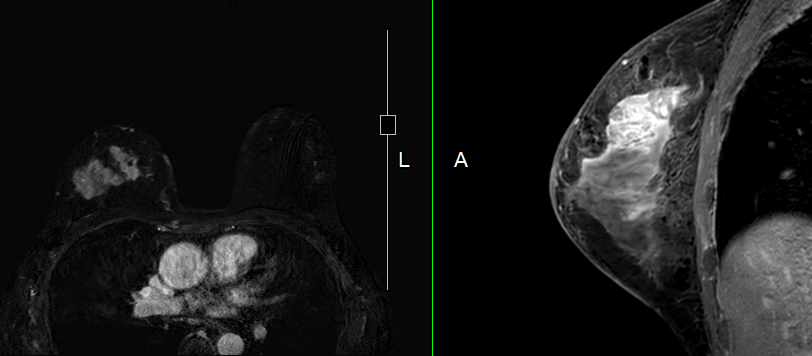

Bởi vì việc khám vú là điều quan trọng đối với mỗi phụ nữ. Ngoài việc chẩn đoán bằng chụp nhũ ảnh và siêu âm là tiêu chuẩn kiểm tra hiện nay. Ngoài ra còn có chẩn đoán vú bằng cách sử dụng hình ảnh cộng hưởng từ. Còn được gọi là Chụp cộng hưởng từ (MRI) được sử dụng để đánh giá kỹ lưỡng vú. Điều này giúp đánh giá sức khỏe vú và sàng lọc ung thư vú hiệu quả hơn. và giúp đưa ra chẩn đoán và kế hoạch điều trị chính xác hơn.

Chụp cộng hưởng từ vú (BREAST MRI) có thể được sử dụng để sàng lọc ung thư vú ở những phụ nữ có nguy cơ cao. Đánh giá các bất thường ở vú rõ ràng hơn ở những bệnh nhân có nhu cầu và có chỉ định khám theo khuyến cáo của bác sĩ chuyên khoa.